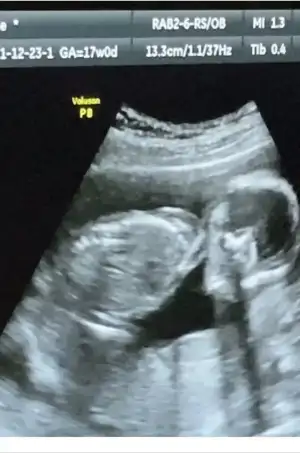

Zaten bir saat sonra göstermeye gideceğim ama anlayan kızlar bi bakabilir mi ya:( iyice doktor olduk nasılsa🤣🤣

Eklentiler

• D02FB9B3-9B2F-4E9A-BBA9-930C5A11C06F.webp

D02FB9B3-9B2F-4E9A-BBA9-930C5A11C06F.webp

17,5 KB · Görüntüleme: 105

Kızlarrrr hajshshsh sürpriz bi şekilde randevum olmuş oldu bugün benim de😂😂😂 öğle arasına girmeden yetişiyim diye koştur koştur gittim en boş doktora verin dedim🤣🤣 adam da bi bet suratlı ama napim artık.

İdrar testi verdim gelmişken bebeğe de bakalım dedi. Ziplenmiş randevu özetim🤣🤣

Peki cinsiyet? Bence kız dedi😳😳😳😳

Önce kız sonra erkek sonra yine kız👀 edepsiz çocuk oynatiiiii annesini. Nifty iyi ki vermişim diyorum yoksa doğumda öğrenecem gerçek cinsiyeti🤣🤣🤣🤣